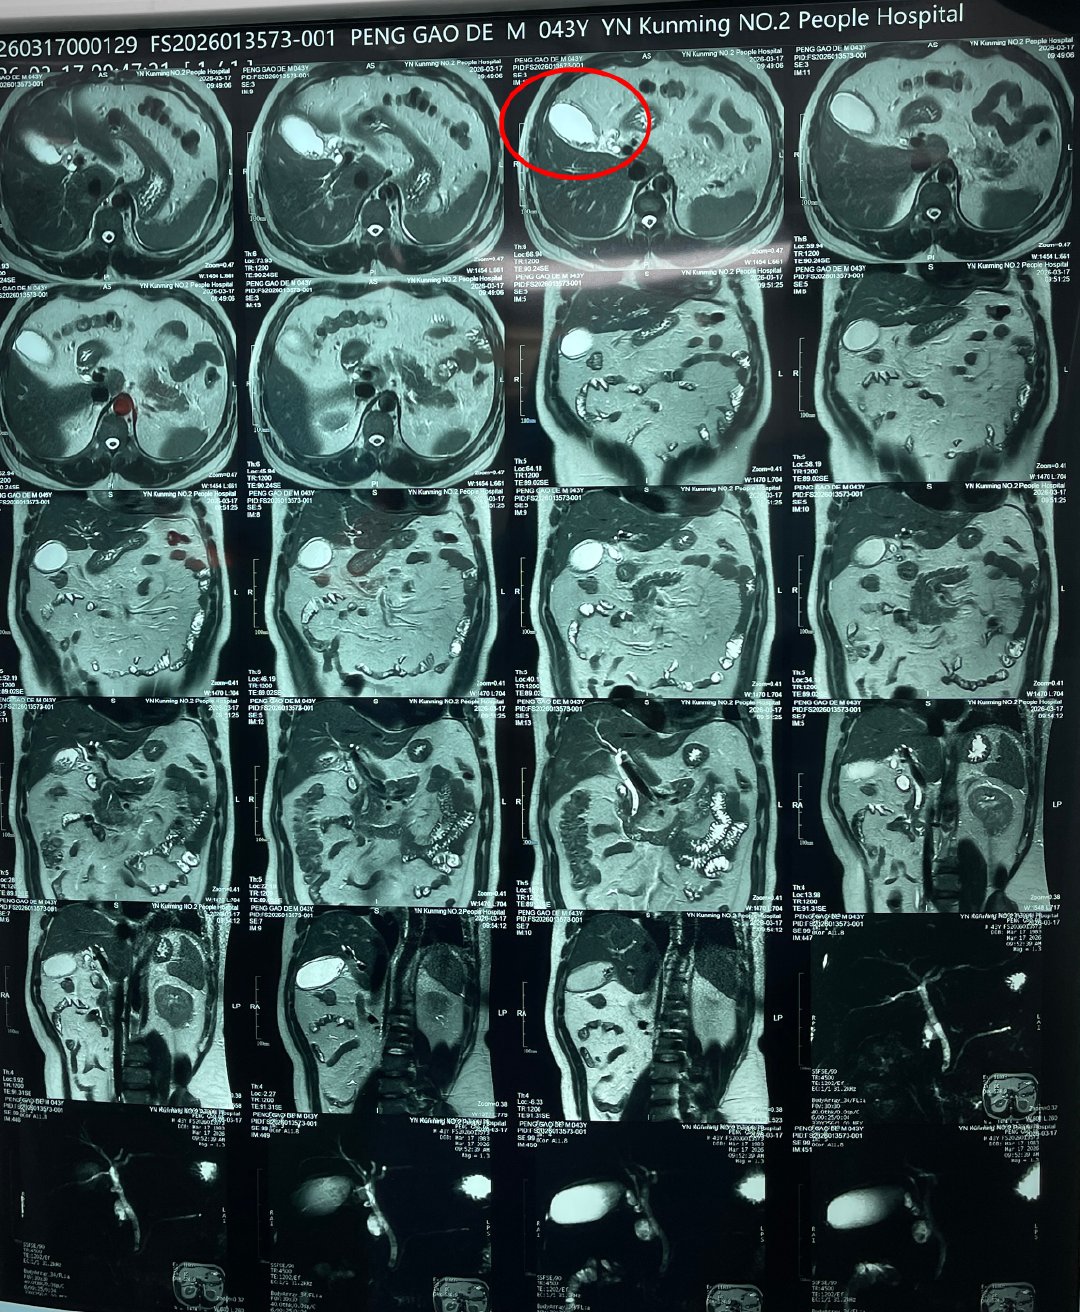

接诊的是肝胆外科王恺主任团队。经详细检查,彭师傅的病情远比想象中危急:胆囊结石伴慢性胆囊炎急性发作,部分胆囊结石掉落至胆总管,引起胆道梗阻、黄疸,导致胆总管结石伴急性化脓性梗阻性胆管炎,并引发了急性胆源性胰腺炎,情况危急。

王恺主任团队立即组织MDT多学科联合会诊,制定手术方案,通过实施微创手术——腹腔镜下胆总管切开探查取石术,精准取出堵塞在胆总管内的结石,帮助彭师傅转危为安。

梗阻解除后,胆囊和胰腺的炎症也得到了有效控制。遗憾的是,经术中评估确认,彭师傅的胆囊功能已完全丧失,无保留价值,团队最终同步为其施行了胆囊切除术。